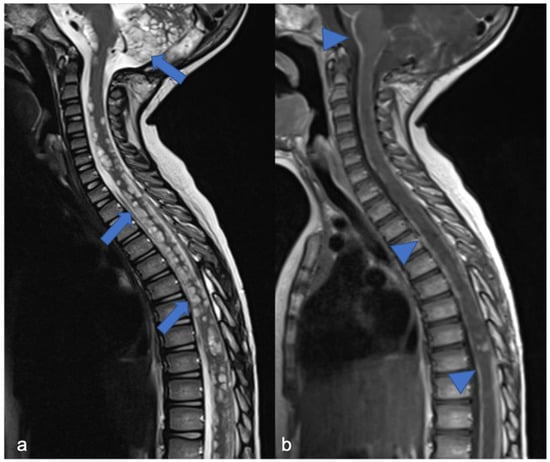

4. Mesenchymal, Non-Meningothelial Tumors